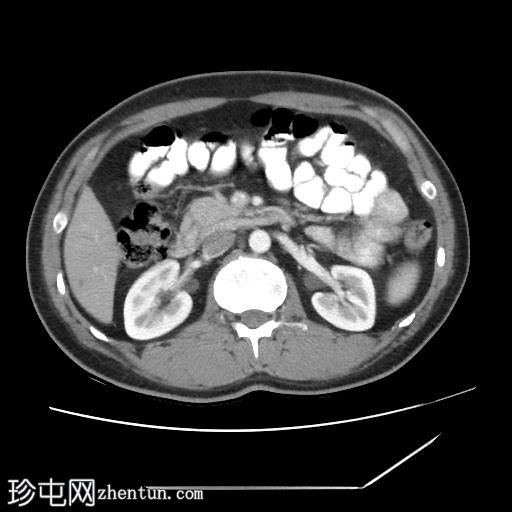

口服造影剂

CT扫描显示胰腺组织完全包绕十二指肠第二段。未发现胰周结节或肿块。

左肝III段可见一低密度囊肿,直径约15 mm。

此外,右肝VII段可见一低密度病灶,呈结节状强化,直径达12 mm,提示肝血管瘤。